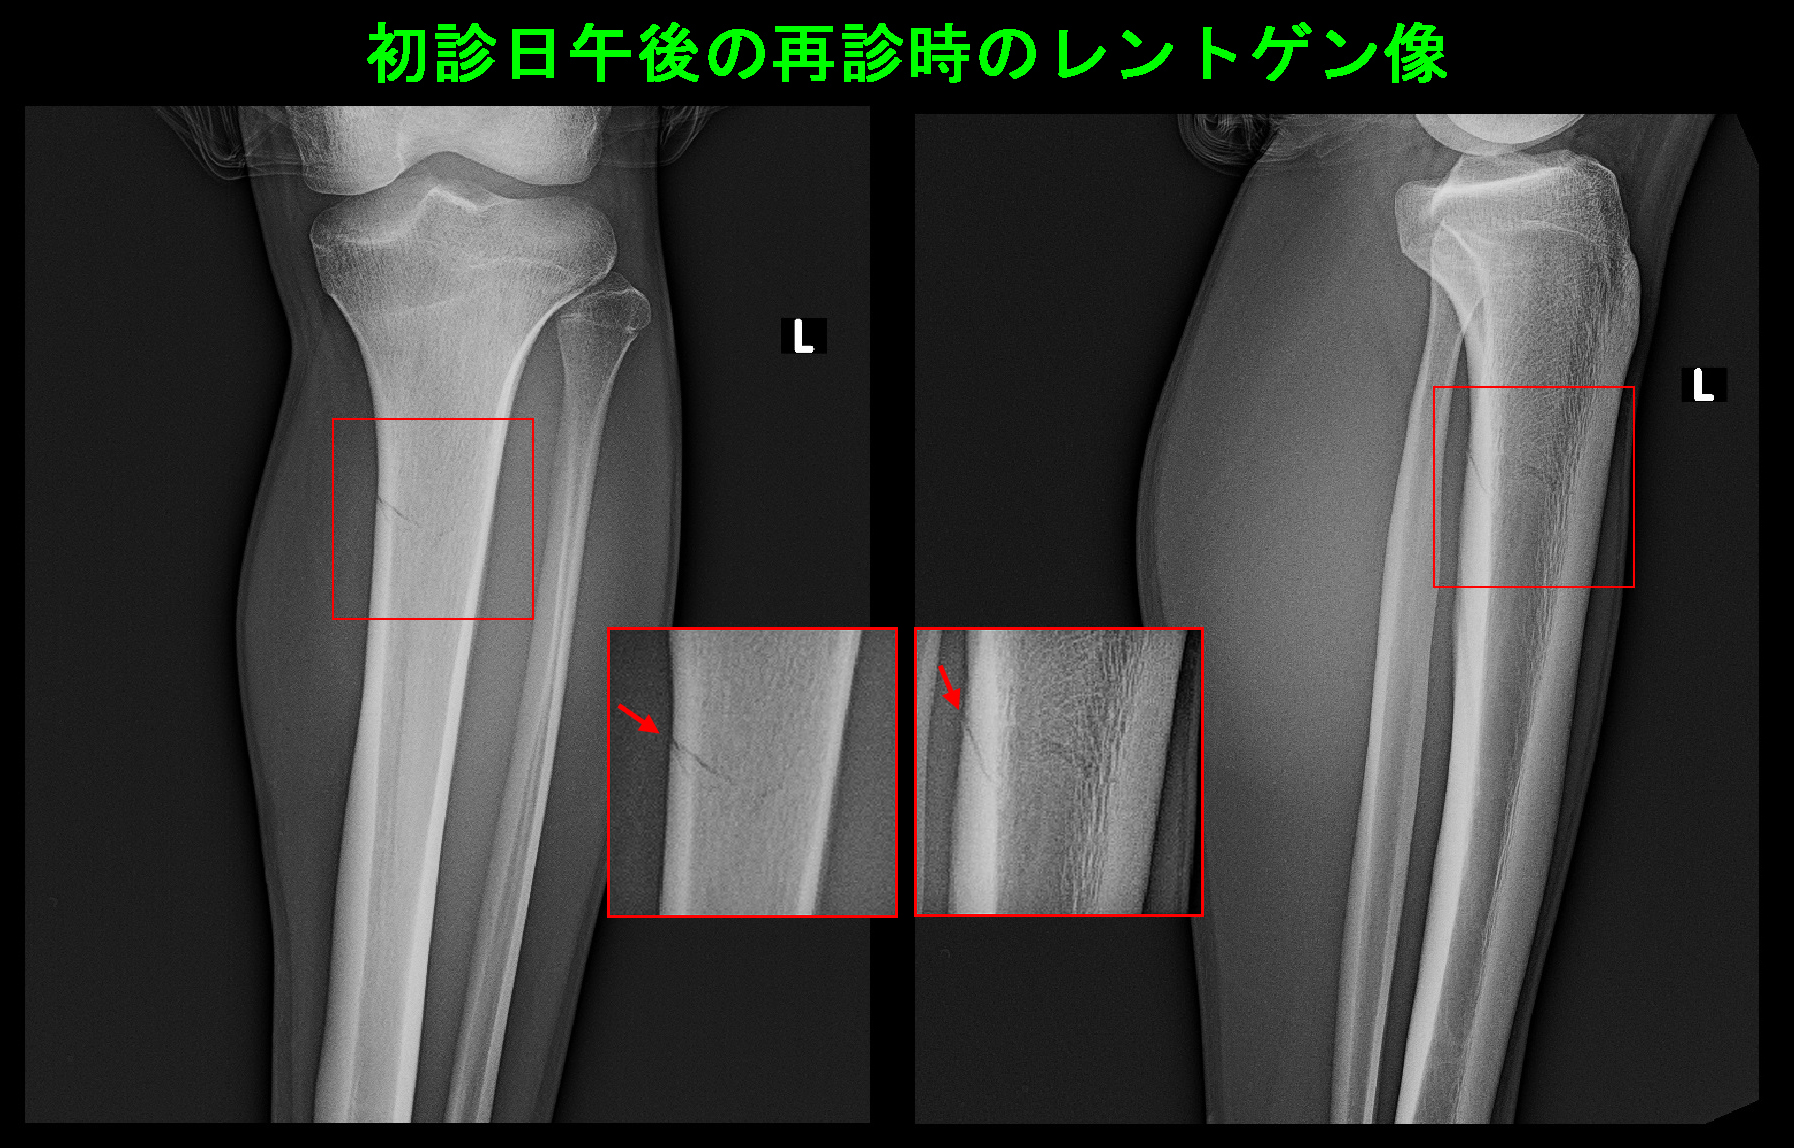

ところが、患者さんは私のアドバイスを本気で受け止めませんでした。受診日の午後の体育でサッカーをして、接触プレーで左下腿がバキっとなり、車イスで再診されたのです。

再診時Xp.jpg

疲労骨折であった脛骨は不全骨折となっていました。松葉杖での免荷歩行(左足をつかずに右脚だけに荷重しての歩行)が4~6週間必要となりました。